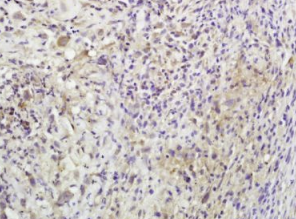

组织/细胞:小鼠淋巴瘤;4%多聚甲醛固定石蜡包埋;

抗原提取:柠檬酸缓冲液(0.01M,pH 6),15min煮沸,用3%过氧化氢阻断内源性过氧化物酶30min;37℃下阻断缓冲液(正常山羊血清)20 min;

孵育:抗β-内啡肽多克隆抗体,未结合1:600,在4°C下过夜,然后与二级抗体结合,DAB染色。